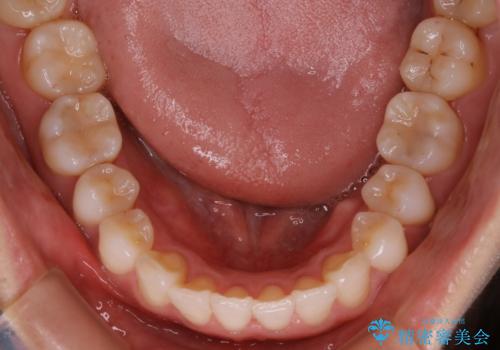

【非抜歯】前歯のガタつき マウスピースの部分矯正

- 上下の前歯の細かいガタつきの治療をご希望されて来院されました。

奥歯部分にはガタつきや噛み合わせの問題などがほとんど見られず、前歯のガタつきも軽度だったため、インビザライン ライト パッケージでの部分矯正を行うこととなりました。

今回のケースでは奥歯の噛み合わせに問題がほぼみられなかったため、前歯の位置のみに焦点を当て部分矯正を行いました。